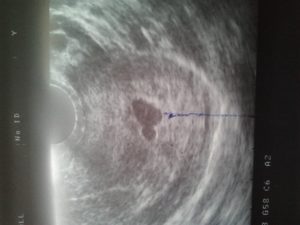

Околоплодное яйцо на УЗИ можно увидеть уже на 4–5 эмбриональной неделе, примерно через 15–20 дней после задержки менструации. Обычно на экране и фото оно выглядит как маленький участок тёмно-серого цвета правильной круглой или овальной формы.

На фото Вы сможете рассмотреть плодное яйцо — небольшое овальное образование. На раннем сроке эмбрион, который будет развиваться в плодном яйце, еще не визуализируется, но скоро он подрастет и будет хорошо виден. Пустое плодное яйцо — это яйцо без эмбриона, когда беременность не развивается.

Фото плодного яйца на УЗИ

При ультразвуковом обследовании на ранних сроках плодное яйцо имеет овальную форму. характеристика при первых обследованиях – внутренний диаметр плодного яйца.